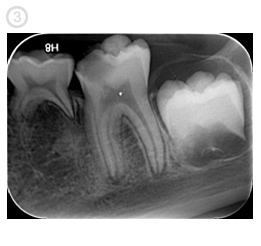

Our digital imaging system offers excellent imaging quality and resolution that is viewed instantly on a computer monitor. It also exposes patients up to 50-90% less radiation when compared to the older X-ray systems. This aids in diagnosis, reduces treatment time and allows the patient to see in detail their completed root canal. (pics 2, 3)